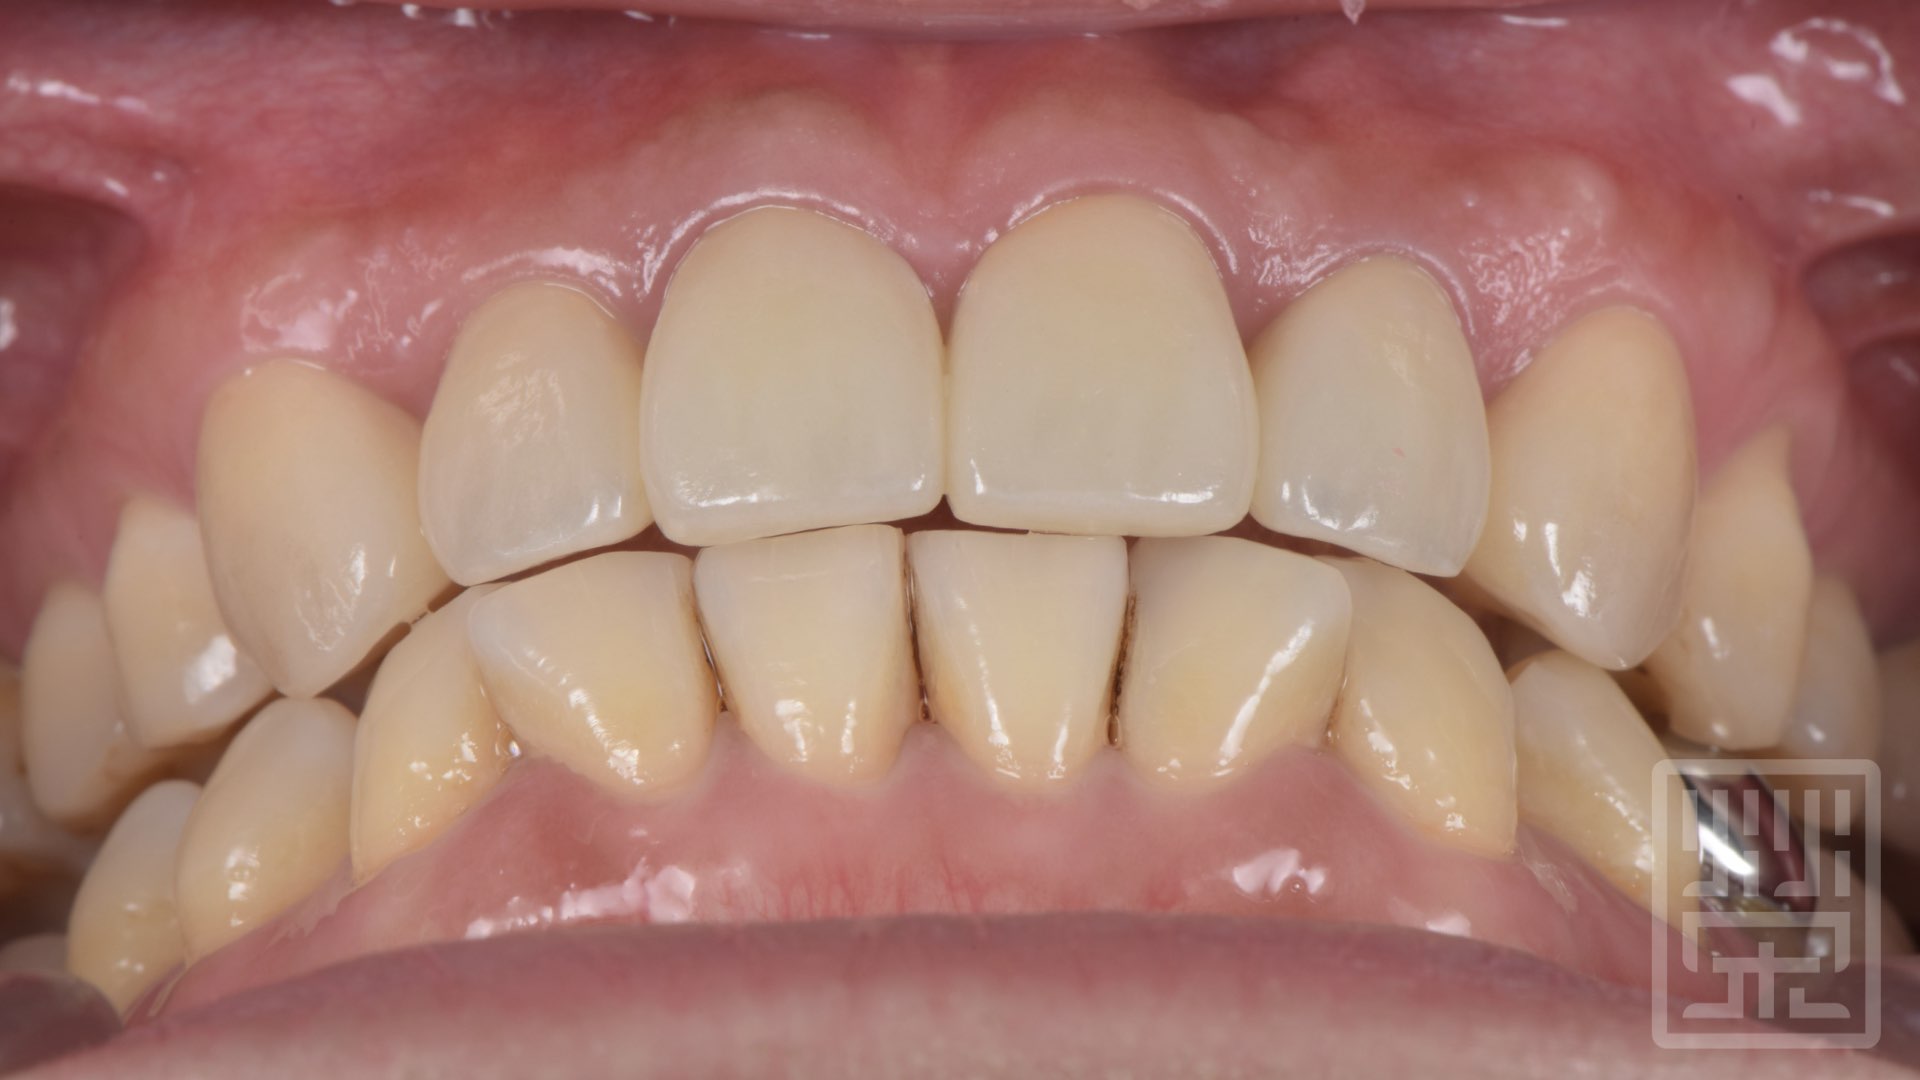

保護性咬合